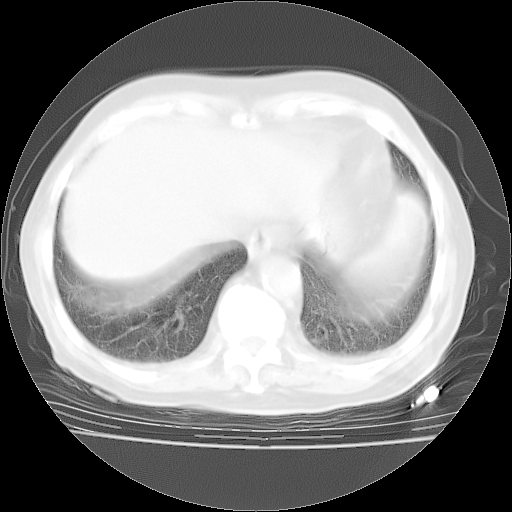

4月28日肺部CT——再次出现类似去年5月9日——磨玻璃样、间有“粟粒样”改变。